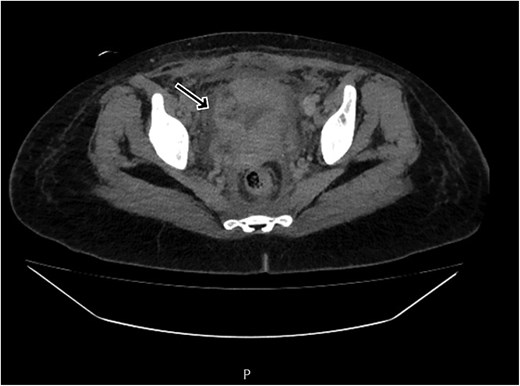

By postpartum day five, the patient exhibited persistent fever and worsening clinical status, unresponsive to broad-spectrum antibiotics. A contrast-enhanced computed tomography (CT) scan was performed, revealing a ruptured uterine scar with omental herniation and a large intra-abdominal abscess (Figs 1 and 2).

CT scan shows a linear small defect in the anterior wall of uterine fundus with small collection (2 × 1 cm).

CT scan revealing a ruptured uterine scar with omental herniation.